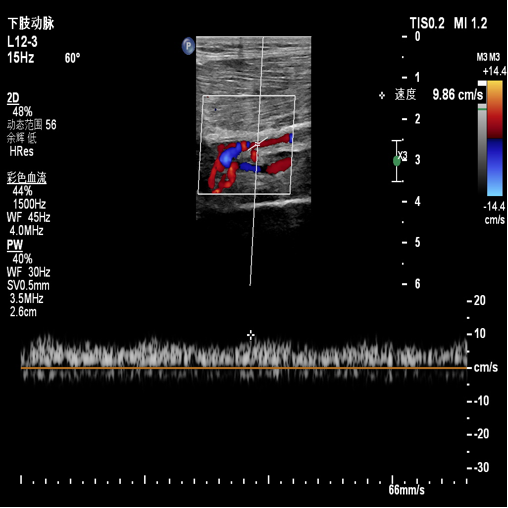

图:a) 穿刺后导丝置入;

图:b) 吸栓装置定位;

图:c) 球囊扩张股浅动脉时球囊远心端显像;

图:d)球囊扩张股浅动脉开口处显像,同时附带血流显像;

图:e)术前评估时腘动脉未见血流图像;

图:f)经吸栓、球囊扩张等治疗措施后腘动脉血流图像